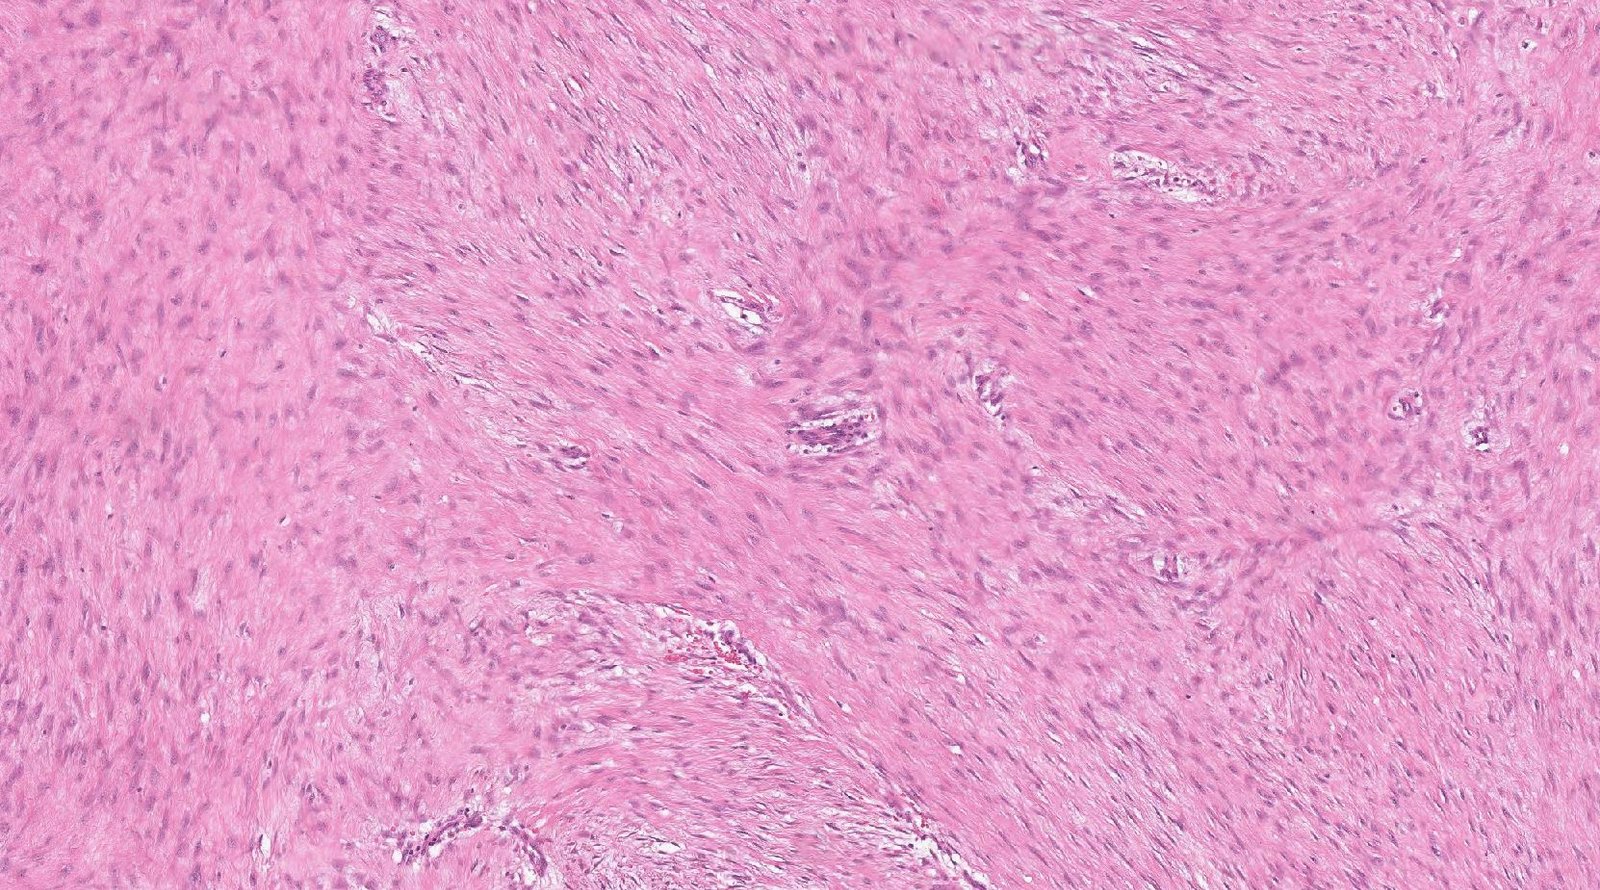

Case: AbdominalMass2

Final Diagnosis: